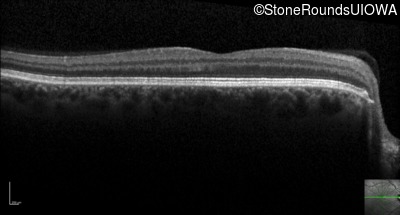

Optical Coherence Tomography - Right - 20/400 sc

Exemplar / OCT Stack